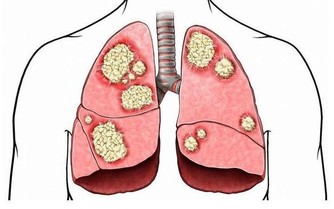

而繼發性腦瘤,是從其他部位(如乳房或肺部)擴散到大腦的癌性生長。

大部分腦腫瘤都屬於這種類型。